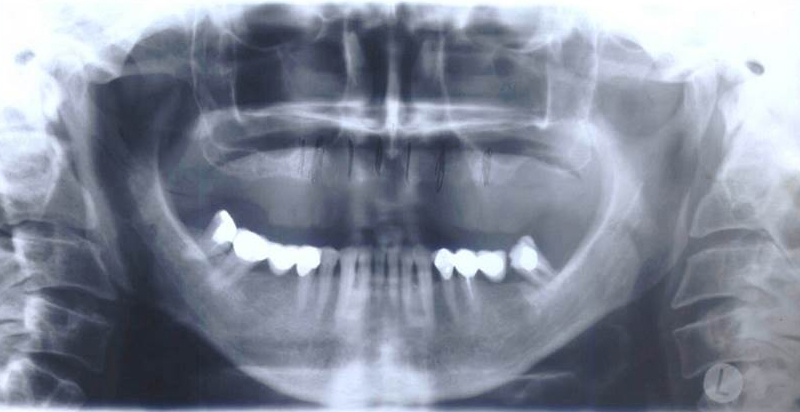

Při ztrátě molárů a premolárů v horní čelisti a jejich náhradě implantáty se často setkáváme s nedostatečnou

vertikální nabídkou kosti pod čelistní dutinou, často doprovázenou i nedostatečnou horizontální nabídkou a sníženou kvalitou kosti (v oblasti 2. premoláru v 50%, v oblasti moláru až v 80% případů nedostatečná kostní nabídka)

Od roku 1985 je tento problém řešen augmentační operací nazývanou

sinus lift.

Jedná se o vyzvednutí membrány, která čelistní dutinu vystýlá, pod vyzvednutou membránou vznikne kapsa, kam se umístí augmentační materiál, do kterého se zavedou implantáty.